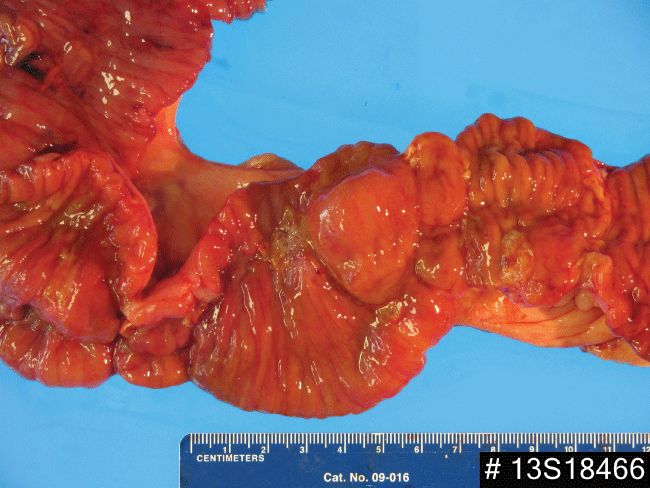

Computed tomography (CT) of the abdomen and pelvis in February 2013 showed mild splenomegaly, mesenteric lymphadenopathy, diffuse sclerosis of the bones, and with mild thickening of the distal colon. Colonoscopy was normal to the terminal ileum. Video capsule endoscopy in April 2013 showed mid-jejunal ulcerations and stenosis. The capsule did not pass into the cecum. His most recent X-ray showed that the capsule was retained. CT enterography on May 7, 2013 showed less than optimal distention of the small bowel proximally, but with an apparent wall thickening of the jejunum in the left mid abdomen with areas of mucosal hyperemia in the ileum and the retained video capsule. Ten days later, a laparotomy with intraoperative enteroscopy (Figure 1 and Figure 2) revealed six tight ulcerated stenoses within a 45cm segment at approximately 120-140 cm from the ileocecal valve. The capsule was stuck at the second stricture. Intra-operative endoscopy was unsuccessful due to the tight and firm strictures. Approximately 45 cm of small bowel was resected.

Figure 1: Intra-operative enteroscopy findings. It showed a tight ulcerated stenosis of the mid-jejunum.

The clinicopathological features of CMUSE have been summarized as follows: (1) chronic iron-deficiency anemia due to small intestinal occult blood loss, (2) rarely diarrhea, malabsorption, hematochezia or fever, (3) unexplained small intestinal strictures found in adolescent and middle-aged subjects, often requiring multiple resections of the small bowel, (4) multiple superficial ulceration of the mucosa and submucosa, predominantly in the ileum (the terminal ileum is usually spared) with infiltration of plasma cells, lymphocytes, and eosinophils, (5) a chronic or relapsing clinical course, even after surgery, (6) no biological signs of systemic inflammatory reaction, C-reactive protein (CRP) and other acute inflammatory reactants remain within normal limits or slightly increased, and (7) beneficial effect of systemic glucocorticosteroids [3,4,7]. Our patient was presented with chronic anemia with melena and recurrent abdominal pain. No diarrhea, malabsorption, hematochezia or fever was documented. His small bowel resection for the strictures with intraoperative enteroscopy revealed six tight ulcerated stenoses. The capsule endoscopy was found to be retained at the second stricture.